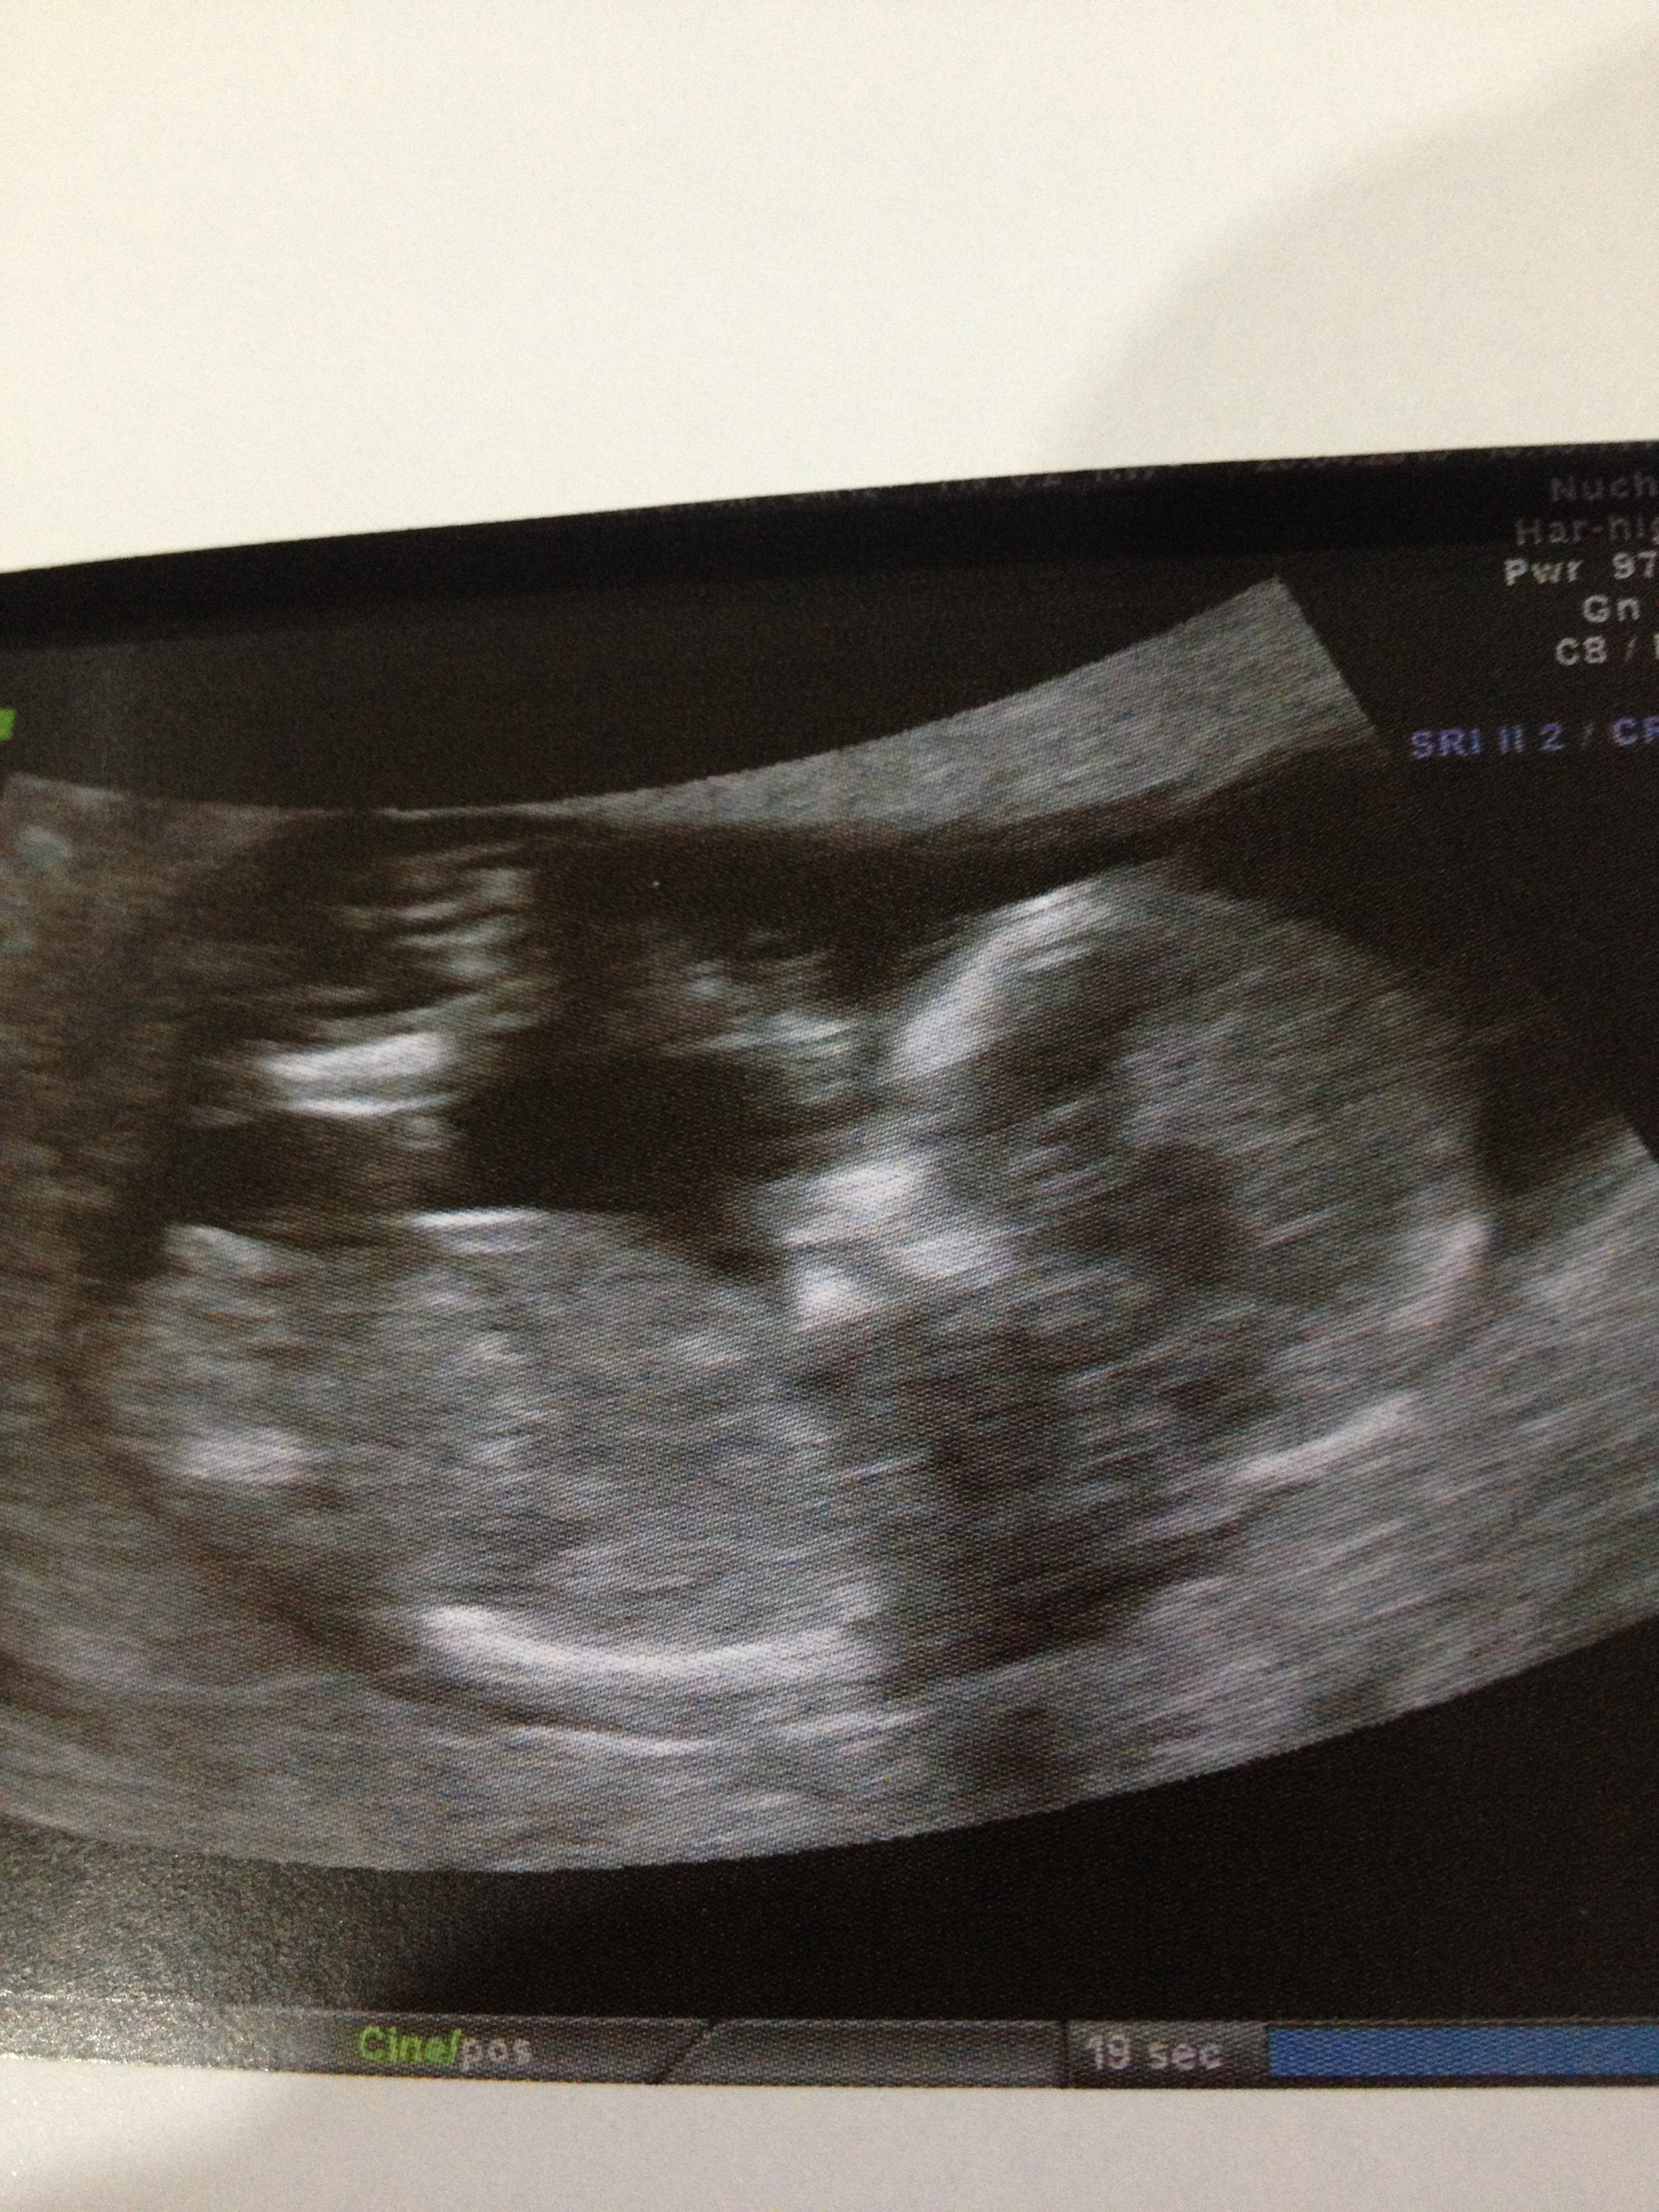

I had my 19 week scan today and bub was confirmed to be a GIRL!!! Thanks everyone for all your support, advice and guesses. Miracles do happen.

Attachment 10778